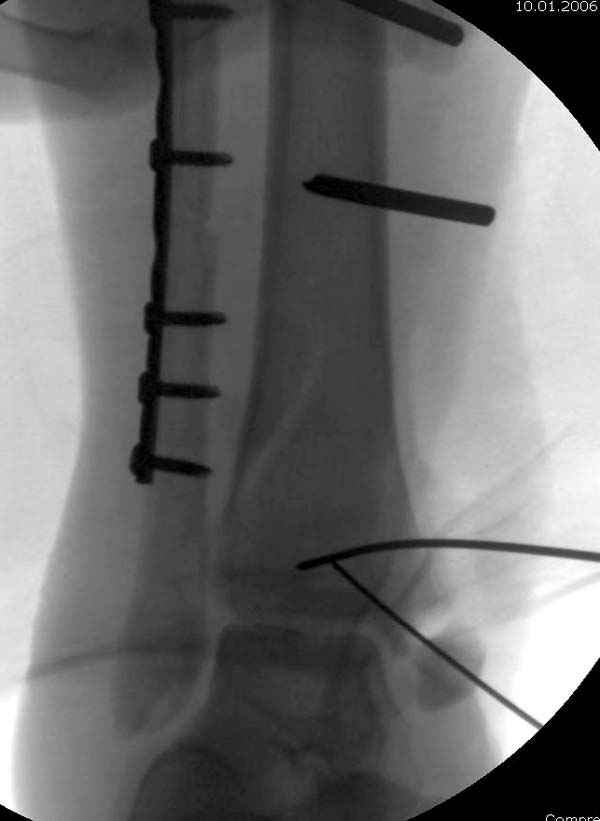

По снимкам довольно сохранный сустав, и такой сустав желательно попытаться восстановить всеми возможными мерами.

Артродез штифтом от Синтеза - немного агрессивно, а для улучшения качества жизни вместо артродеза голеностопа можно было бы предложить артродез подтаранного сустава. Тремя 6.5 мм каннюлированными шурупами через пятку.

Насчет пилона, прошло достаточное время для консолидации и прекрасная возможность для демонстрации, что такие случаи могут быть успешно вылечены остеотомией, несмотря на засторелость.

Из заднего доступа остеотомия тонким остеотомом и коррекции на ЭОПе.

Без применения сложной конструкции, а обычными параллельными шурупами. Шурупы в 3.5 мм и дополнительно фиксация крючковидной пластиной, сделанной из 3.5 mm semitubular пластиной, Butress или аntiglade фиксация.

Здесь алгоритм фиксации свежего перелома и преоперационный план для обсуждаемого случая.